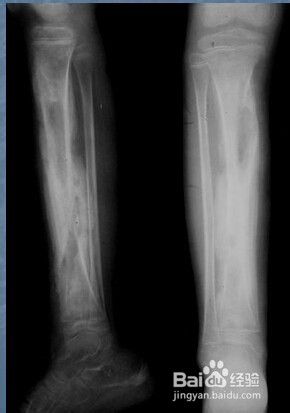

一:急性化脓性骨髓炎X线。

2. 2

二:慢性化脓性骨髓炎X线。